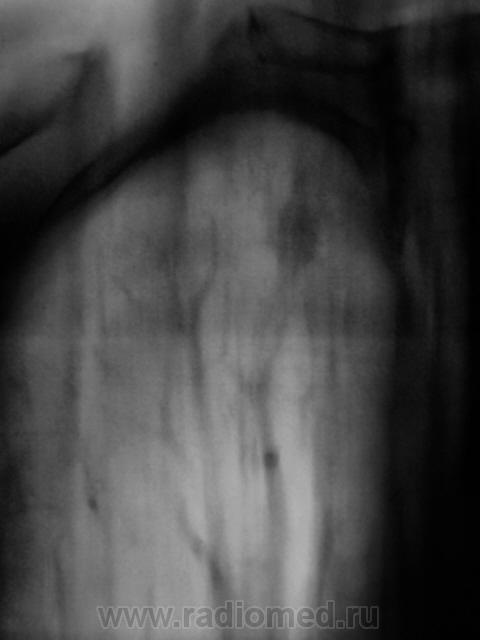

При исследовании верхушек использую в основном срезы (с прицелом на туб. процесс) - 7,8,9 см., правда, есть поправка на конституцию пациента и упитанность пациента. При боковой томографии, при патологии именно лёгкого отправными срезами являются 7, 8см. с коррекцией на вышеуказанное.

При выборе среза в прямой проекции, глубину среза выбираю по боковой, а для боковой томографии, руководствуюсь "прямой проекцией"

А справа на верхушке то не туберкулома?

да, туберкулома